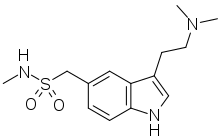

| Sumatriptan | artificial | 5-(CH2SO2NHCH3) | CH3 | CH3 | 1-[3-(2-Dimethylaminoethyl)-1H-indol-5-yl]-N-methyl-methanesulfonamide | 103628-46-2 |